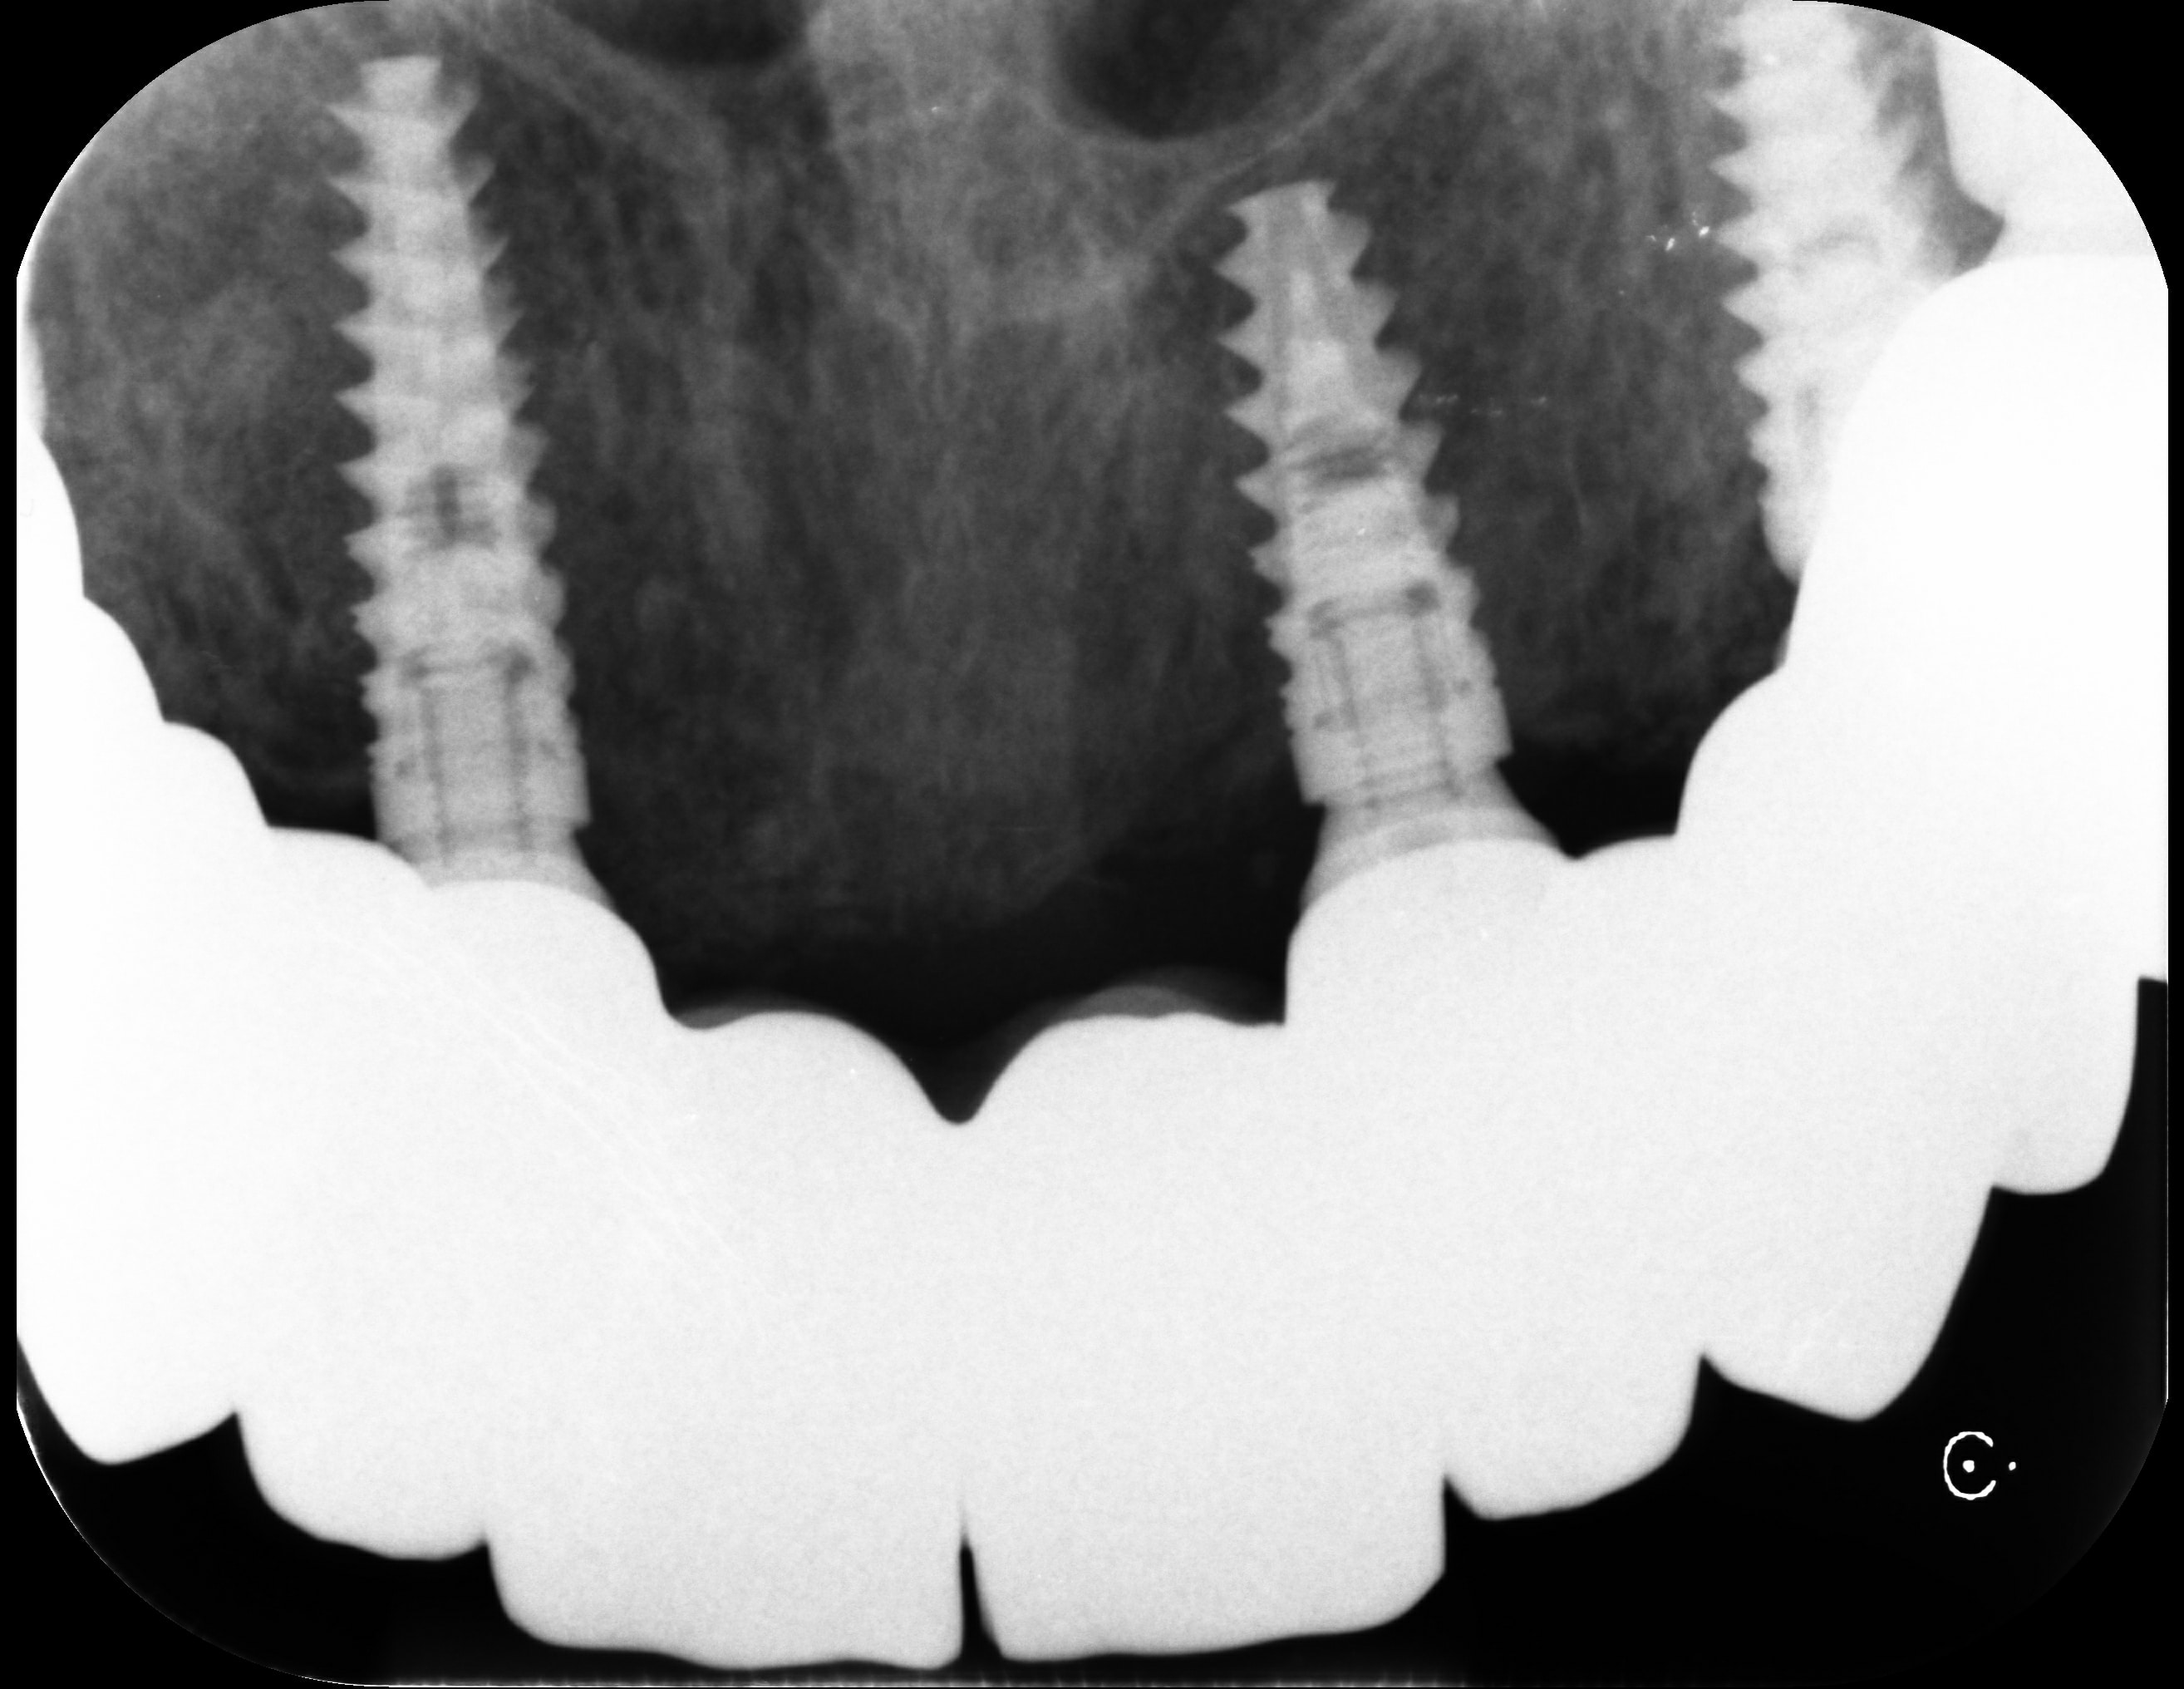

Nei campi di concentramento più grandi c’era sempre anche lo studio del dentista. I dentisti delle SS lavoravano sotto il comando del medico generale del campo. L’oro dentale recuperato dai prigionieri morti, era anche utilizzato per curare gli ufficiali.

Oltre 100 dentisti SS furono impiegati nei campi, di cui almeno 60 identificati con certezza.

Sette dentisti furono condannati per crimini di guerra, tra cui Hugo Blaschke, il dentista personale di Hitler, Himmler e Göring, responsabile dell’organizzazione della raccolta dell’oro dentale. Sorprende che fu condannato a soli 10 anni di prigione.

La Procedura di Estrazione

All’arrivo nei campi, veniva eseguito un esame medico di ogni prigioniero. Anche i dentisti delle SS avevano potere di vita o di morte sui nuovi prigionieri. Potevano decidere di ucciderli all’istante o inviarli al “lavoro”. In ogni caso, i denti d’oro sarebbero stati recuperati sempre, prima o dopo.

I corpi con denti d’oro venivano marcati con una croce blu o un filo corto su un dito. L’oro raccolto veniva inviato mensilmente al comando con una ricevuta che indicava il peso recuperato.

Ad Auschwitz, un team odontoiatrico apriva le bocche dei morti subito dopo le camere a gas ed estraeva tutti i denti d’oro con le pinze. Nel 1943 fu creata addirittura una fonderia d’oro nel Crematorio III. Secondo il sopravvissuto Filip Müller, venivano fusi da 5 a 10 kg al giorno, modellati in lingotti da 140 grammi.